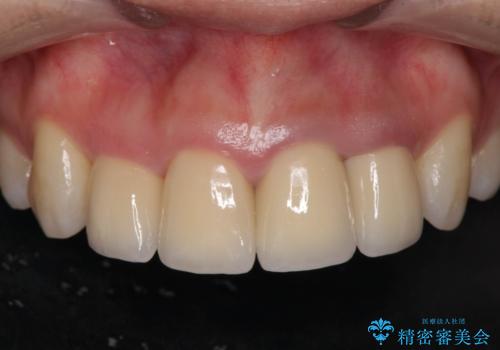

装着されているクラウンを除去し、自然な色調のジルコニアクラウンによる審美生の改善、インプラントを用いた欠損部の機能回復を計画します。

自然な仕上がりとインプラントによる咬合機能の回復に満足いただくことができました。